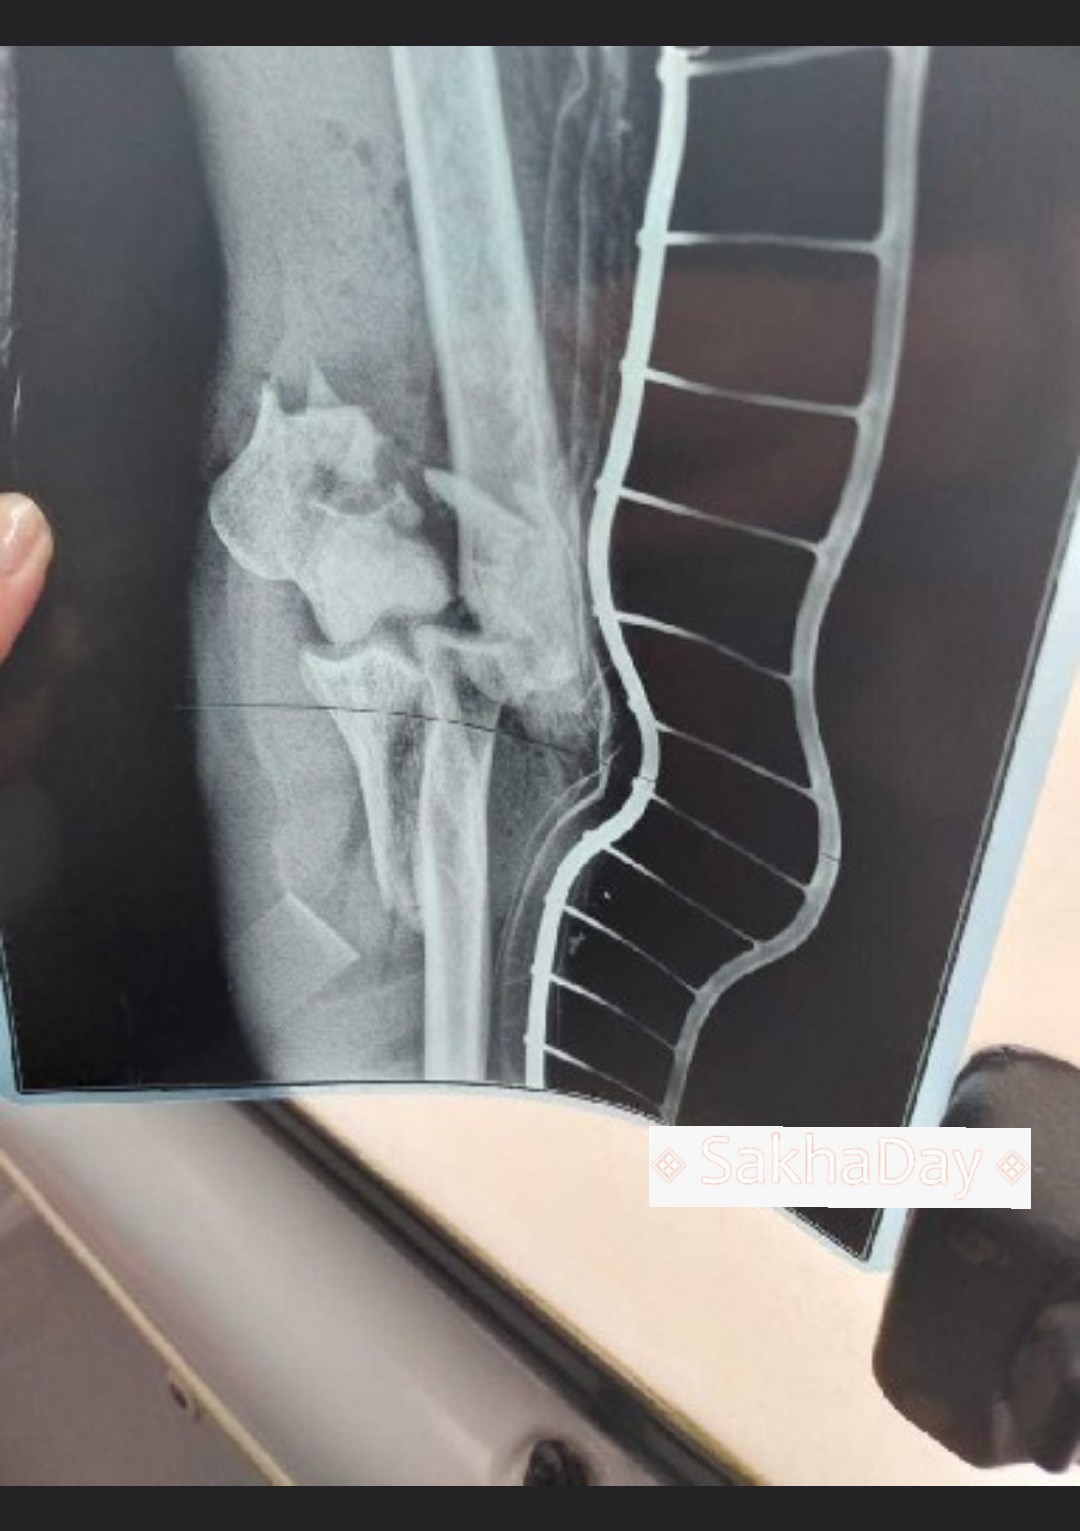

– Меня взрослого человека не могло сдуть ветром от проезжающей мимо фуры. И мои травмы не сопоставимы с обычным падением с велосипеда. На фото видно, что также ударом снесло левое зеркало велосипеда. В больнице сказали, что если бы фура сбила на 10 см правее, то мне бы снесло голову!

Когда сидишь за рулем велосипеда, то локти выставляются в стороны. Так вот, у меня сильно повреждена локтевая кость, рваные раны. При падении травмировал кисьь руки, не могу пальцем.